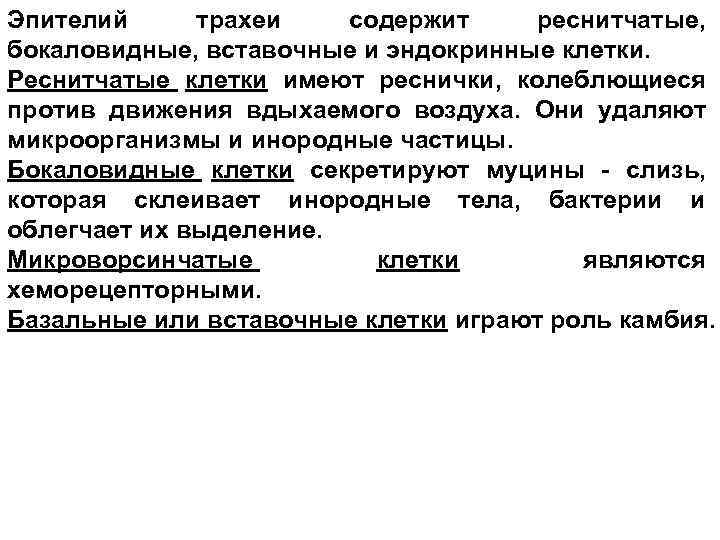

Эпителий трахеи содержит реснитчатые, бокаловидные, вставочные и эндокринные клетки. Реснитчатые клетки имеют реснички, колеблющиеся против движения вдыхаемого воздуха. Они удаляют микроорганизмы и инородные частицы. Бокаловидные клетки секретируют муцины - слизь, которая склеивает инородные тела, бактерии и облегчает их выделение. Микроворсинчатые клетки являются хеморецепторными. Базальные или вставочные клетки играют роль камбия.